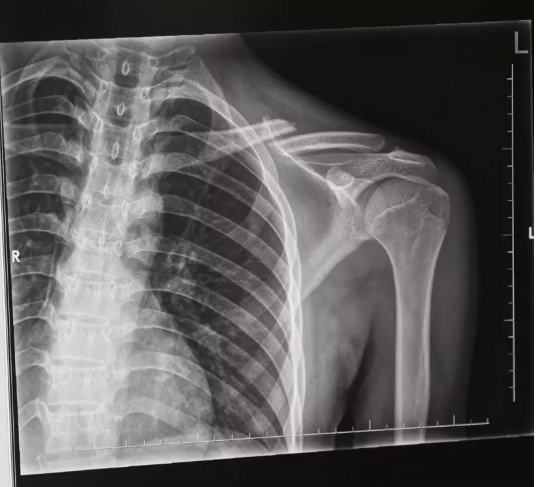

随后,马某某带着年轻男子来到杨庙镇医院检查,经拍X光片,医生诊断这名自称“丁某某”的伤者锁骨骨折,需要手术。见此情形,与“丁某某”同行者以两人无法做主为由,致电一位自称年轻男子亲戚的人。后再与这位亲戚上商量中,其以小伙不是本地人,需要回老家做手术为由,最终让马某某赔偿了一万元。过了一段时间,马某某越想越觉得可疑,3月28日,他拨打110报了警

长丰县公安局刑警大队在接警后,根据马某某的描述,并到达事发地医院进行走访得知,受伤的“丁某某”只拍了一个X光片,没有基本的治疗,直接拿钱走人,且双方还未曾互留联系方式,这点引起了警方的注意。

随后,警方对周边城市所有医院在最近的拍的X光片进行核查,发现3月17日至4月7日间,在寿县、凤台、长丰、肥西的多家医院均有名为“丁某某”的锁骨骨折的X光片子。后经过监控录像辨认,发现“丁某某”均为同一人,且均无治疗情况。据此警方认定这是一个碰瓷团伙,于是成立专案组。

经审讯,曾某某、何某某为首的诈骗团伙长期实施碰瓷诈骗。他们分工明确,由曾某某在东莞等地招募20岁以下年轻男性,承诺给予10%-20%的利润后,设法把他们的锁骨弄骨折。在这些小伙骨折期间,他们就带着小伙前往各地,专挑小路且没有保险的三轮摩托车伺机碰瓷。

曾某某等人开车物色受害人,再利用车辆挡住前面道路,趁着三轮车超车之时,让小伙伪装成被撞摔倒。等去医院拍片确认骨折后,何某某等人给受害人施压,每次诈骗一万元左右。

“因为拍片可以看出新伤还是旧伤,所以该团伙每雇一个小伙,就利用愈合前的十天内疯狂作案,等到伤口开始愈合后就换人。”办案民警告诉记者,在这十天的时间内,他们选择市郊或县城附近监控较少地区,疯狂作案。而受雇的小伙,基本都是在广东打工,受到每次4、5万元的高额利润的诱惑选择铤而走险,成为了曾某某、何某某等人诈骗的工具。